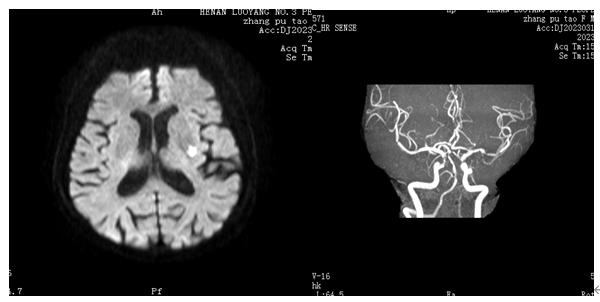

图4 左侧基底节区急性孤立性梗死灶,同侧MCA狭窄(图源 作者提供)

穿支动脉分布区的急性孤立梗死灶,载体动脉存在斑块或任何程度狭窄的证据。例如,发生在基底节区的急性孤立梗死灶,在同侧MCA分布区不存在其它急性梗死病灶;或者在脑桥发生的急性孤立梗死灶,而在基底动脉供血区内不存在其他急性梗死病灶。该急性孤立梗死灶推断是甶载体动脉的斑块突出后堵塞了穿支动脉的血流所致。